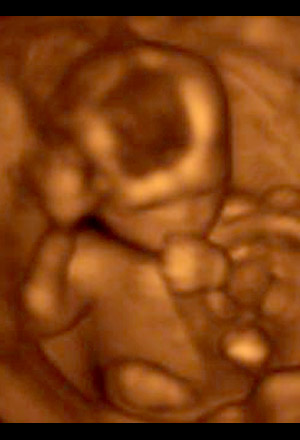

The placenta has taken over production of the hormones needed to sustain your pregnancy. The fetus now measures about 11 cm (4.4 inches) and weighs about 85 grams (3 ounces). Most of the baby's organs are formed, and the gender may be detectable by ultrasound. By 16 weeks, the baby has eyelids, finger and toe nails. The baby starts sensing sounds and light, is able to suck and swallow, and has an activity schedule that includes naps.